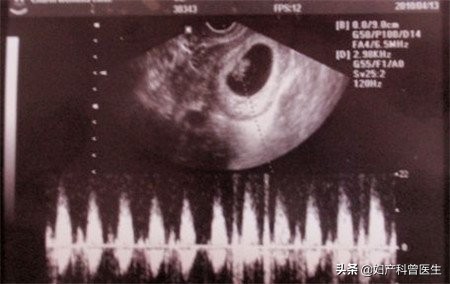

第一次:停经约6-8周

大概是停经50天左右,检查孕囊的情况(宝宝居住的"房子"),查看胚芽大小可推测孕周,如有胎心管搏动,就表示小生命有心跳了。早孕超声还有一个重要的目的就是肯定是否为宫内妊娠,排除宫外孕及葡萄胎,查看单胎还是多胎。

孕囊:宝宝居住的"房子"